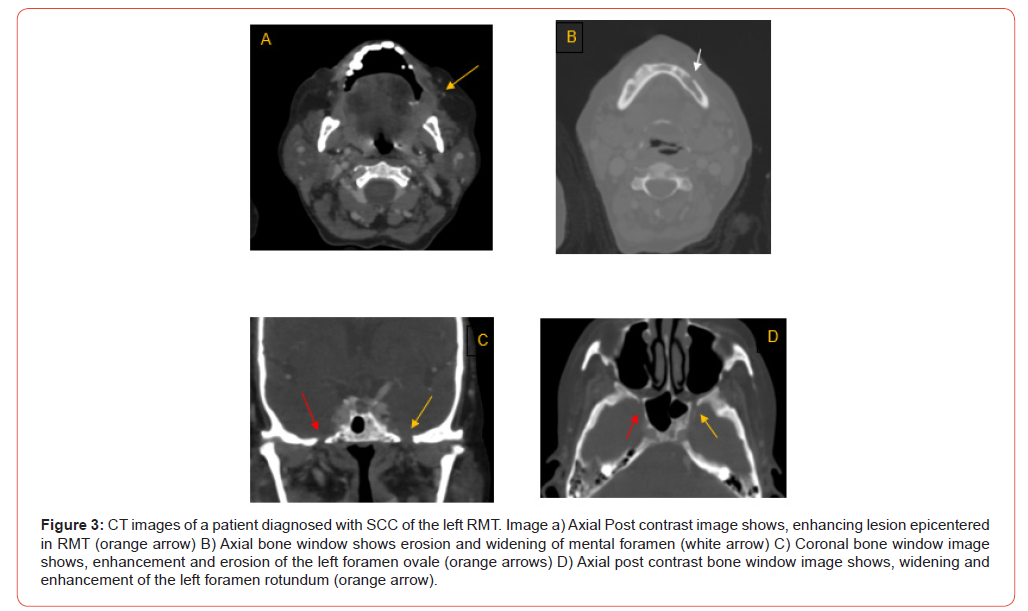

24 out of 100 patients had PNS on CT (Table 6, Figures 1-5), whereas 26 of 100 patients had histopathologically proven PNS. The two methods agreed in 88.0% of the cases and disagreed in 12.0% of the cases. There was a statistically significant agreement between the two variables, with kappa value of 0.680. Sensitivity, specificity, PPV, NPV and diagnostic accuracy of CT images for the detection of PNS were 73.1%, 93.2%, 79.2%, 90.8% and 88% respectively (Table 7). The most common nerve involved was mandibular nerve followed by maxillary nerve. Strongest predictors of PNS included foraminal widening, nerve thickening, and muscle denervation (Table 8).

Analysis of TNM staging indicated that advanced-stage tumors (III and IV) showed a higher prevalence of PNS. However, statistically, no significant relation was seen between the T and N stage of tumour and presence of PNS (Figure 6 and 7). Anatomical patterns revealed that PNS was most common in the buccal mucosa, followed by tongue, retro-molar trigone, alveolus, gingiva-buccal sulcus and hard palate (Figure 8).

The study also aimed to identify patterns of PNS involvement across different anatomical subsites. Results showed that PNS along maxillary nerve was most frequently associated with OSCC in buccal mucosa, RMT, and hard palate; while PNS along mandibular nerve was more common in OSCC affecting buccal mucosa, RMT, lower alveolus, and tongue. These patterns align with studies by Parker GD, et al. [13] and Caldemeyer KS, et al. [14] which reported that OSCC spread along mandibular and maxillary nerves often follows primary tumors in these locations. Such findings are significant for surgical planning, as they highlight specific nerve pathways that may require more intensive examination and possible resection to achieve clear margins.